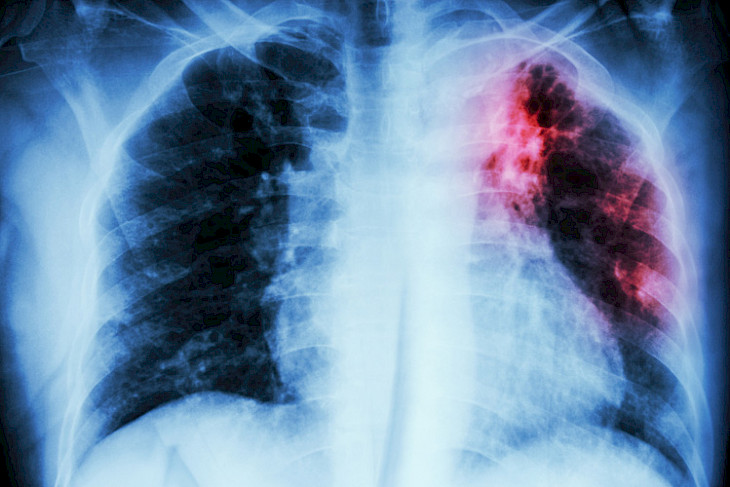

Бишкек, 20.02.18 /Кабар/. Жалал-Абад шаарында 2017-жылы кургак учук оорусуна кабылгандар саны 2016-жылга салыштырмалуу аз болгон. Бирок, бул оору боюнча эпидемилогиялык абал курч бойдон калууда. Бул тууралуу шаардык кургак учукка каршы диспансеринин башкы дарыгери Акылбек Ормонбеков билдирди.

Анын айтымында, 2016-жылы 93 адамдан бул оору биринчи жолу табылган болсо, өткөн жылы анын саны 89 болгон. Ооругандыгы аныкталгандардын ичинен 73ү чоң кишилер, өспүрүмдөр жок. Бирок, жаш балдар арасынан 2016-жылы 8и ооруга чалдыкканы аныкталса, өткөн жылы алардын саны эки эсеге өсүп, 16ны түзгөн. Бардык 89 ооруган кишинин ичинен 64ү дем алуу органдарынын кургак учук оорусу, 20сы жугуштуу түрү менен, 50сү инфильтративдүү кургак учук менен, 28и өтүшүп кеткен түрү менен, 9у дисиминирлештирилген кургак учук менен ооруган. Дагы 25 киши өпкөдөн башка органдардын кургак учугуна чалдыккан.